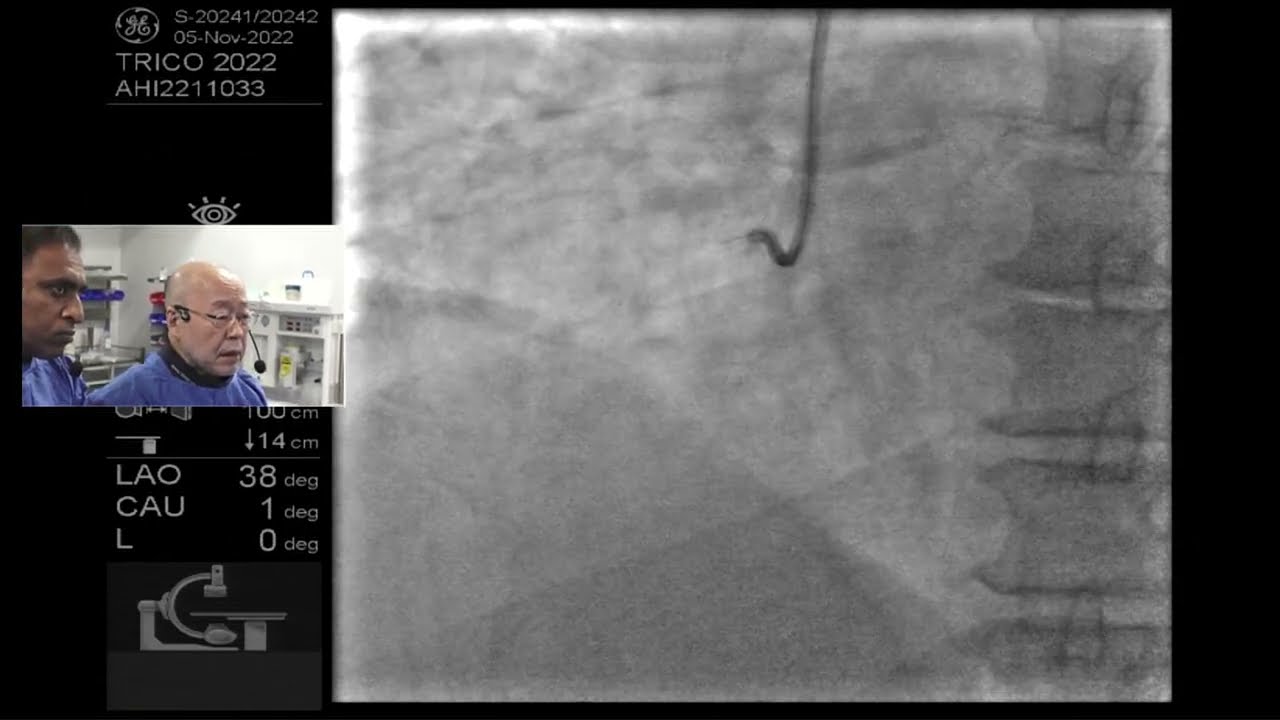

The sixth case was a very complex CTO of RCA done by Dr. Shigeru Saito with Rajni. He is considered as one of the “World Gurus” for CTO. He did everything to address the lesion. There was an intense discussion between the panel and Dr. Saito. Although the case was not successful the audience loved watching Dr. Saito doing this case.